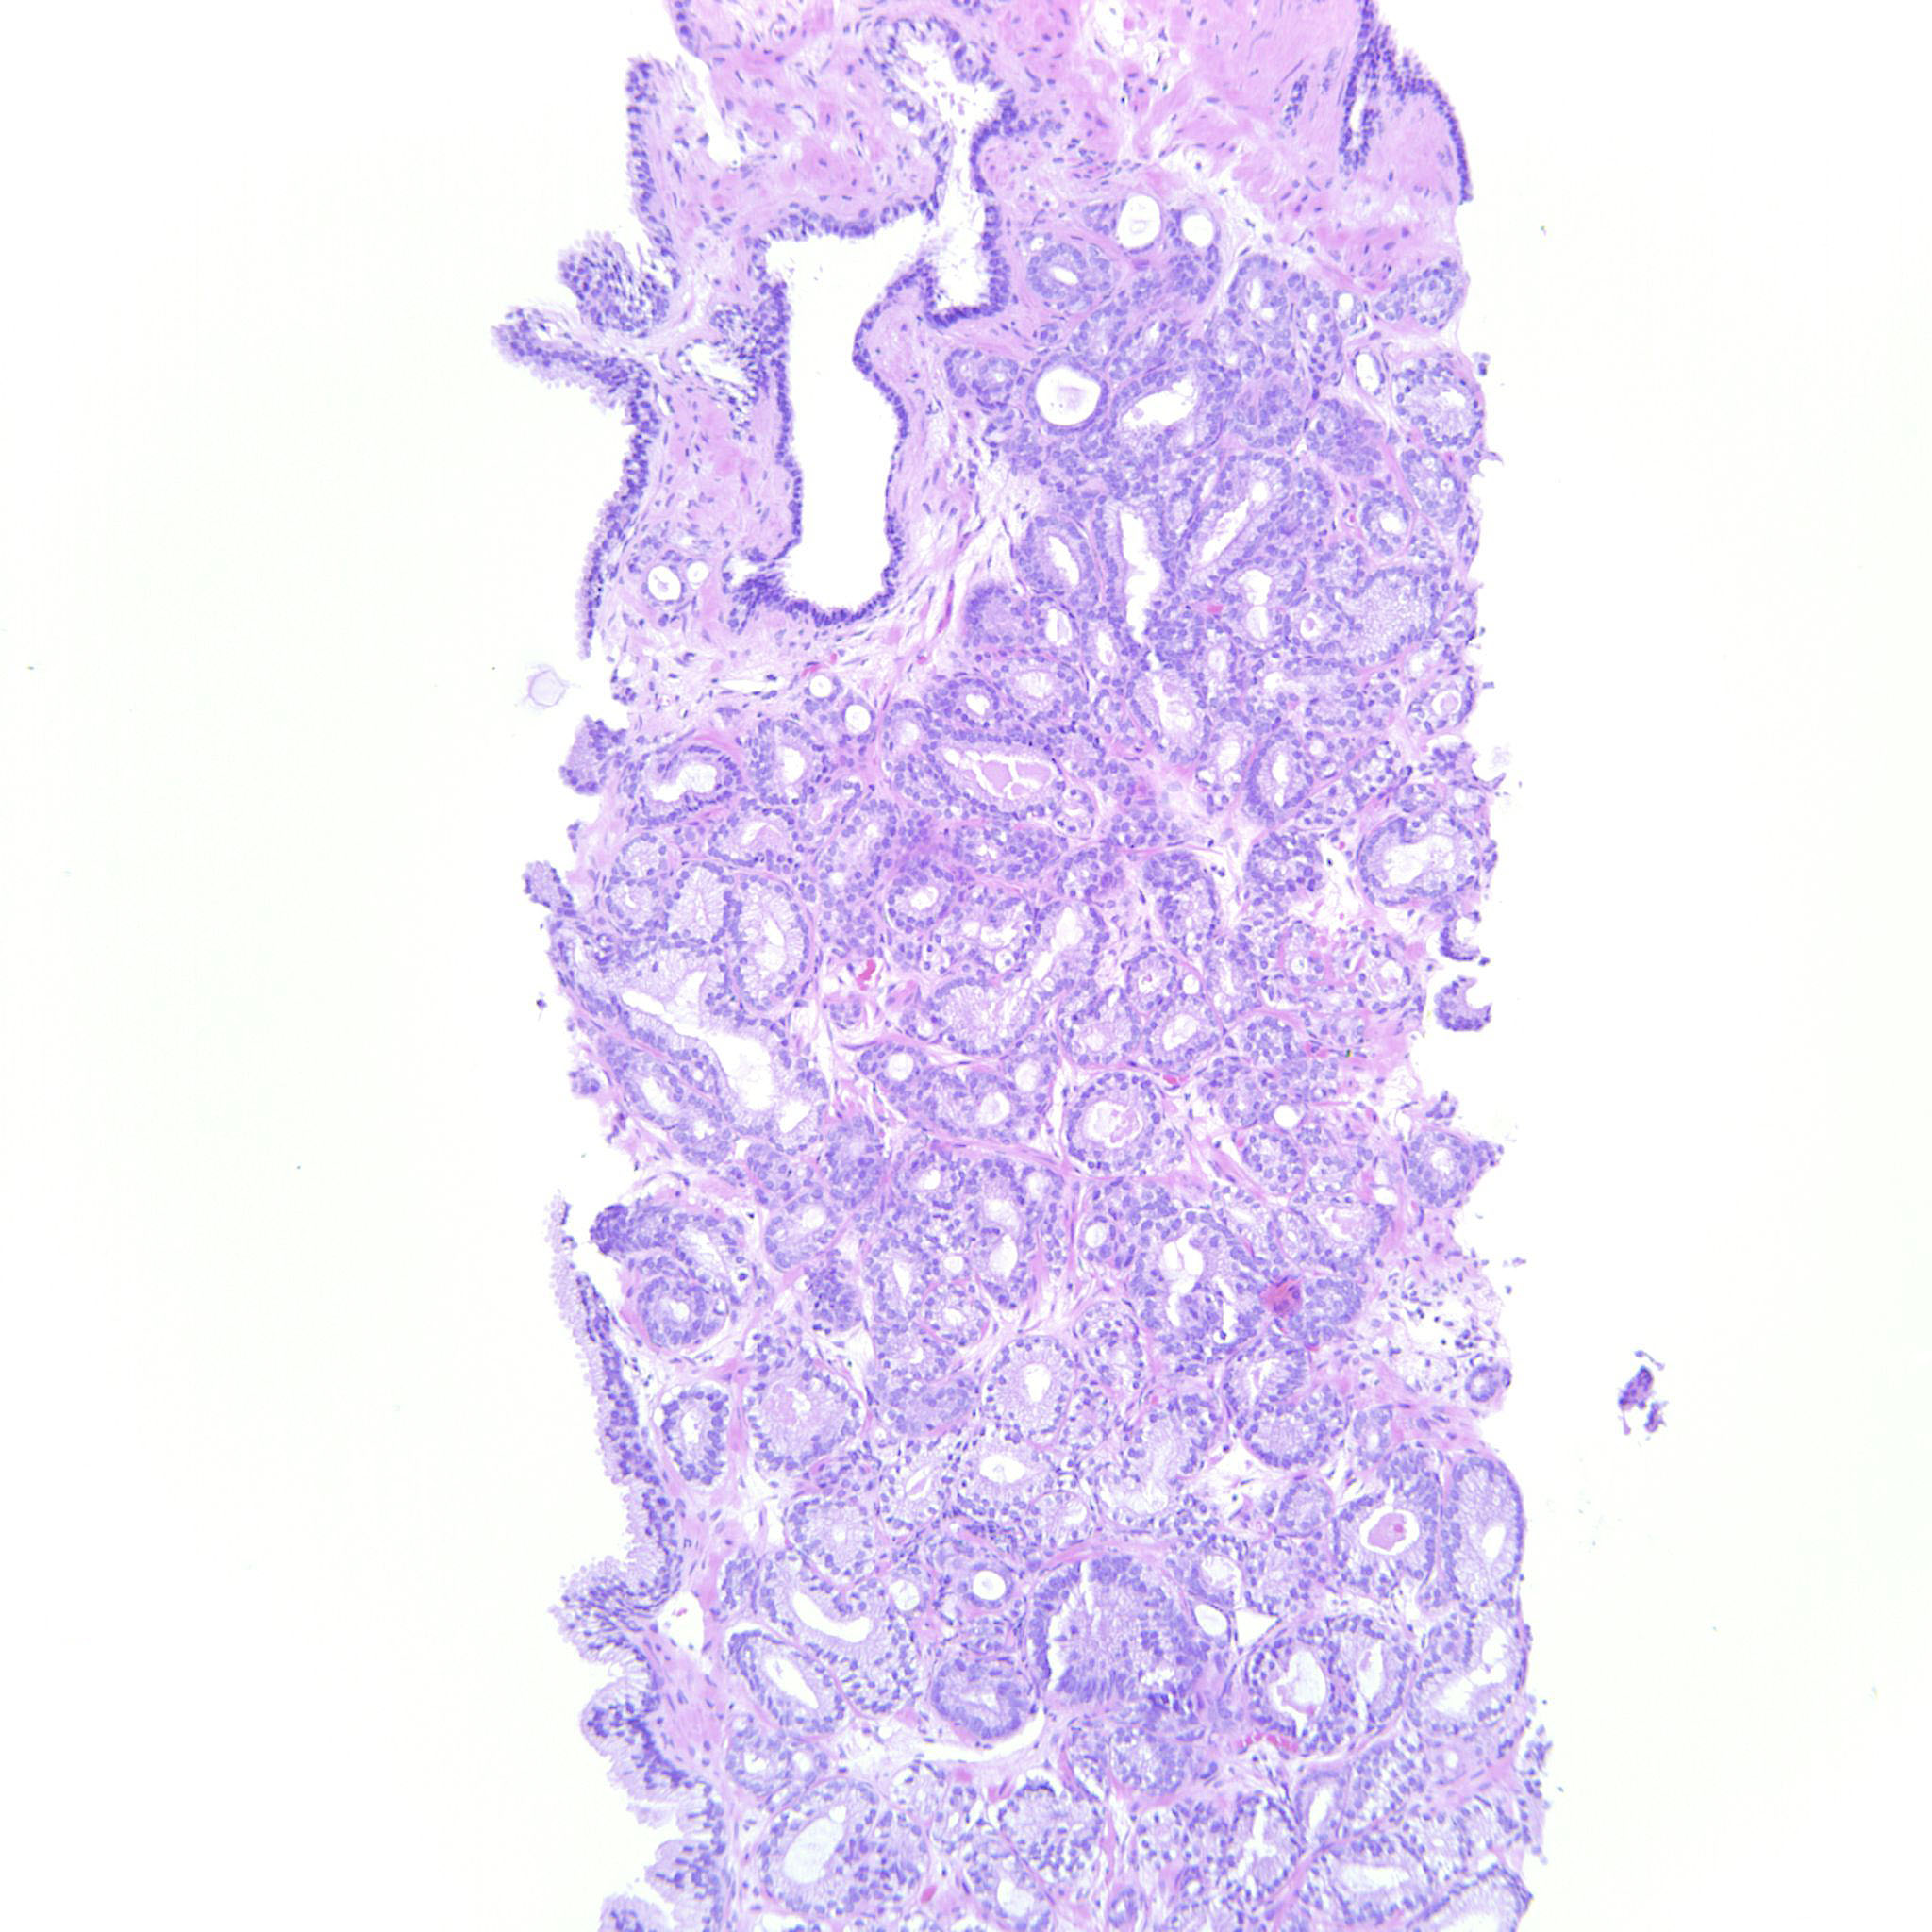

Case ID: 151

Consensus grade: GS 3+3=6 (ISUP 1)

Case description (by case creator):

3+3=6 with occasional seemingly poorly formed glands. These are however seen between well-formed glands and probably represent tangential cuts.